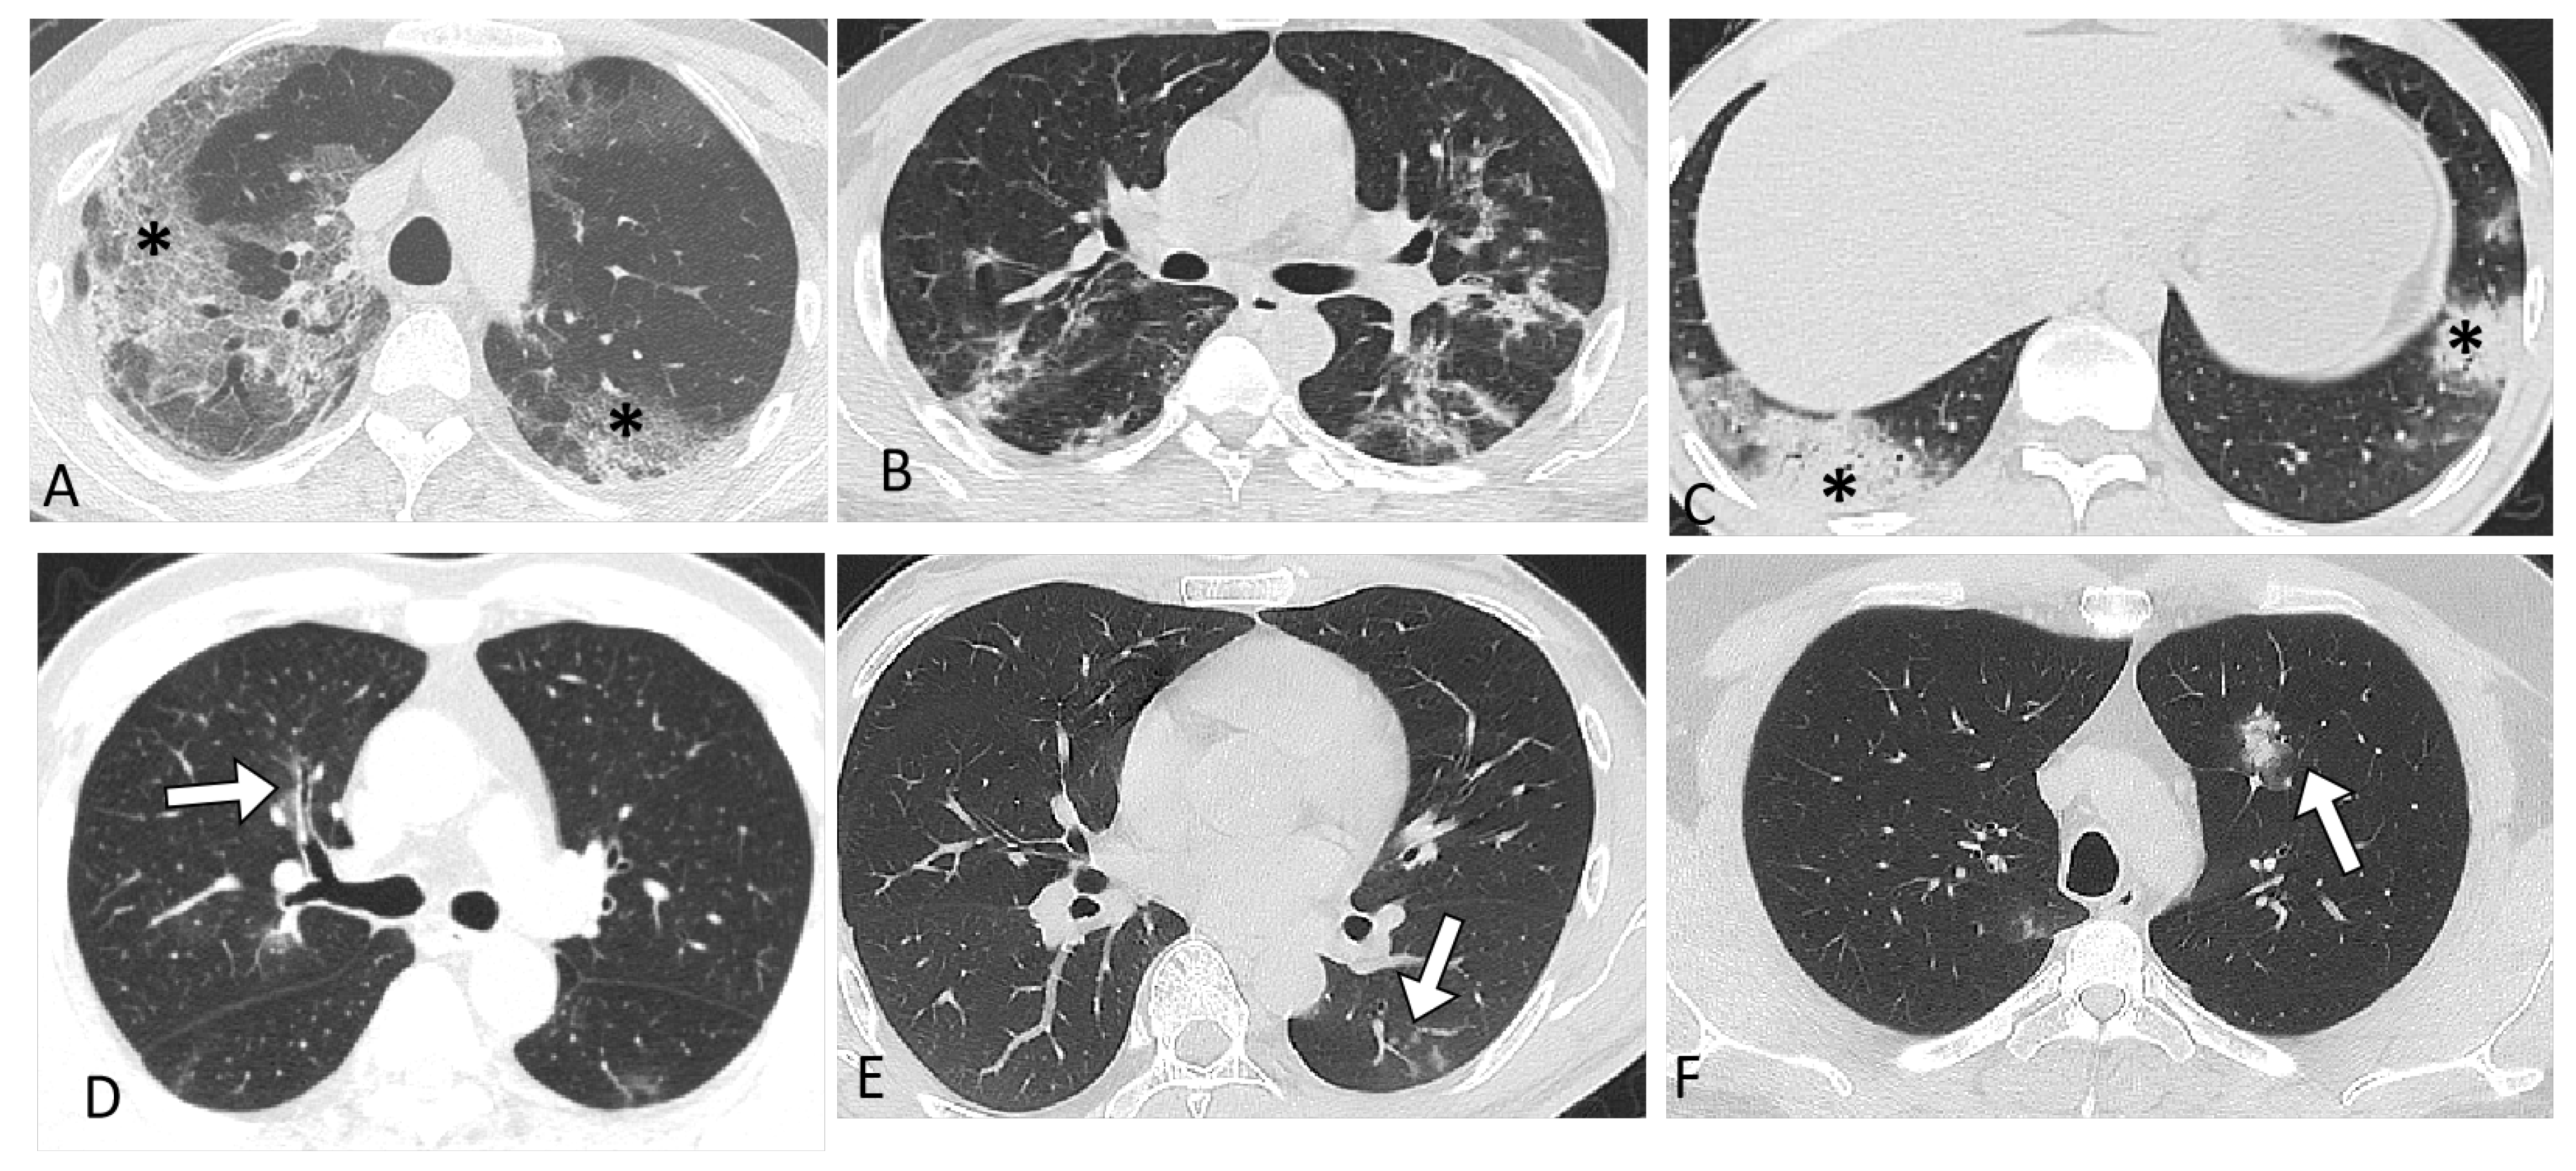

| CT Characteristics | Original Strain (n = 245) | Delta Variant (n = 90) | Omicron Variant (n = 168) | p Value |

|---|---|---|---|---|

| CT scan thickness | <0.001 | |||

| 1.25 mm | 140 (57.1%) | 90 (100%) | 168 (100%) | |

| 5 mm | 105 (42.8%) a | 0 | 0 | |

| Abnormal CT | 235 (95.9%) a,b | 73 (81%) c | 73 (44%) | <0.001 |

| COVID-19 pneumonia imaging classification | <0.001 | |||

| Typical appearance | 228 (97%) | 55 (75%) | 48 (66%) | |

| Indeterminate appearance | 3 (1.3%) | 8 (11%) | 13 (18%) | |

| Atypical appearance | 4 (1.7%) | 10 (14%) | 12 (16%) | |

| Lesions involvement | <0.001 | |||

| Unilateral | 9 (3.8%) a | 17 (23%) | 9 (12%) | |

| Bilateral | 226 (96.2%) a | 56 (77%) | 64 (88%) | |

| CT score of total lesions | 14 (9.0–20.0) a,b | 6.0 (3.0, 8.5) | 5.0 (3.0, 10) | <0.001 |

| Predominant CT pattern | 0.093 | |||

| GGO | 176 (74.9%) a,b | 45 (62%) | 48 (66%) | |

| Consolidation | 44 (18.7%) | 18 (25%) | 20 (27%) | |

| Linear and reticulation | 15 (6.4%) | 10 (14%) | 5 (6.8%) | |

| Crazy paving | 79 (33.6%) a,b | 14 (19%) | 10 (14%) | |

| Thickening of the bronchial wall | 51 (21.8%) | 7 (9.6%) | 20 (28%) | 0.009 |

| Nodule or mass | 8 (3.4%) a,b | 6 (8.2%)c | 17 (23%) | <0.001 |

| Tree-in-bud sign | 0 a,b | 4 (5.5%) | 6 (8.2%) | <0.001 |

| Halo sign | 4 (1.6%) a,b | 5 (6.8%) | 10 (14%) | <0.001 |

| pleural effusion | 37 (15.7%) a | 8 (11%) | 4 (5.5%) | 0.063 |